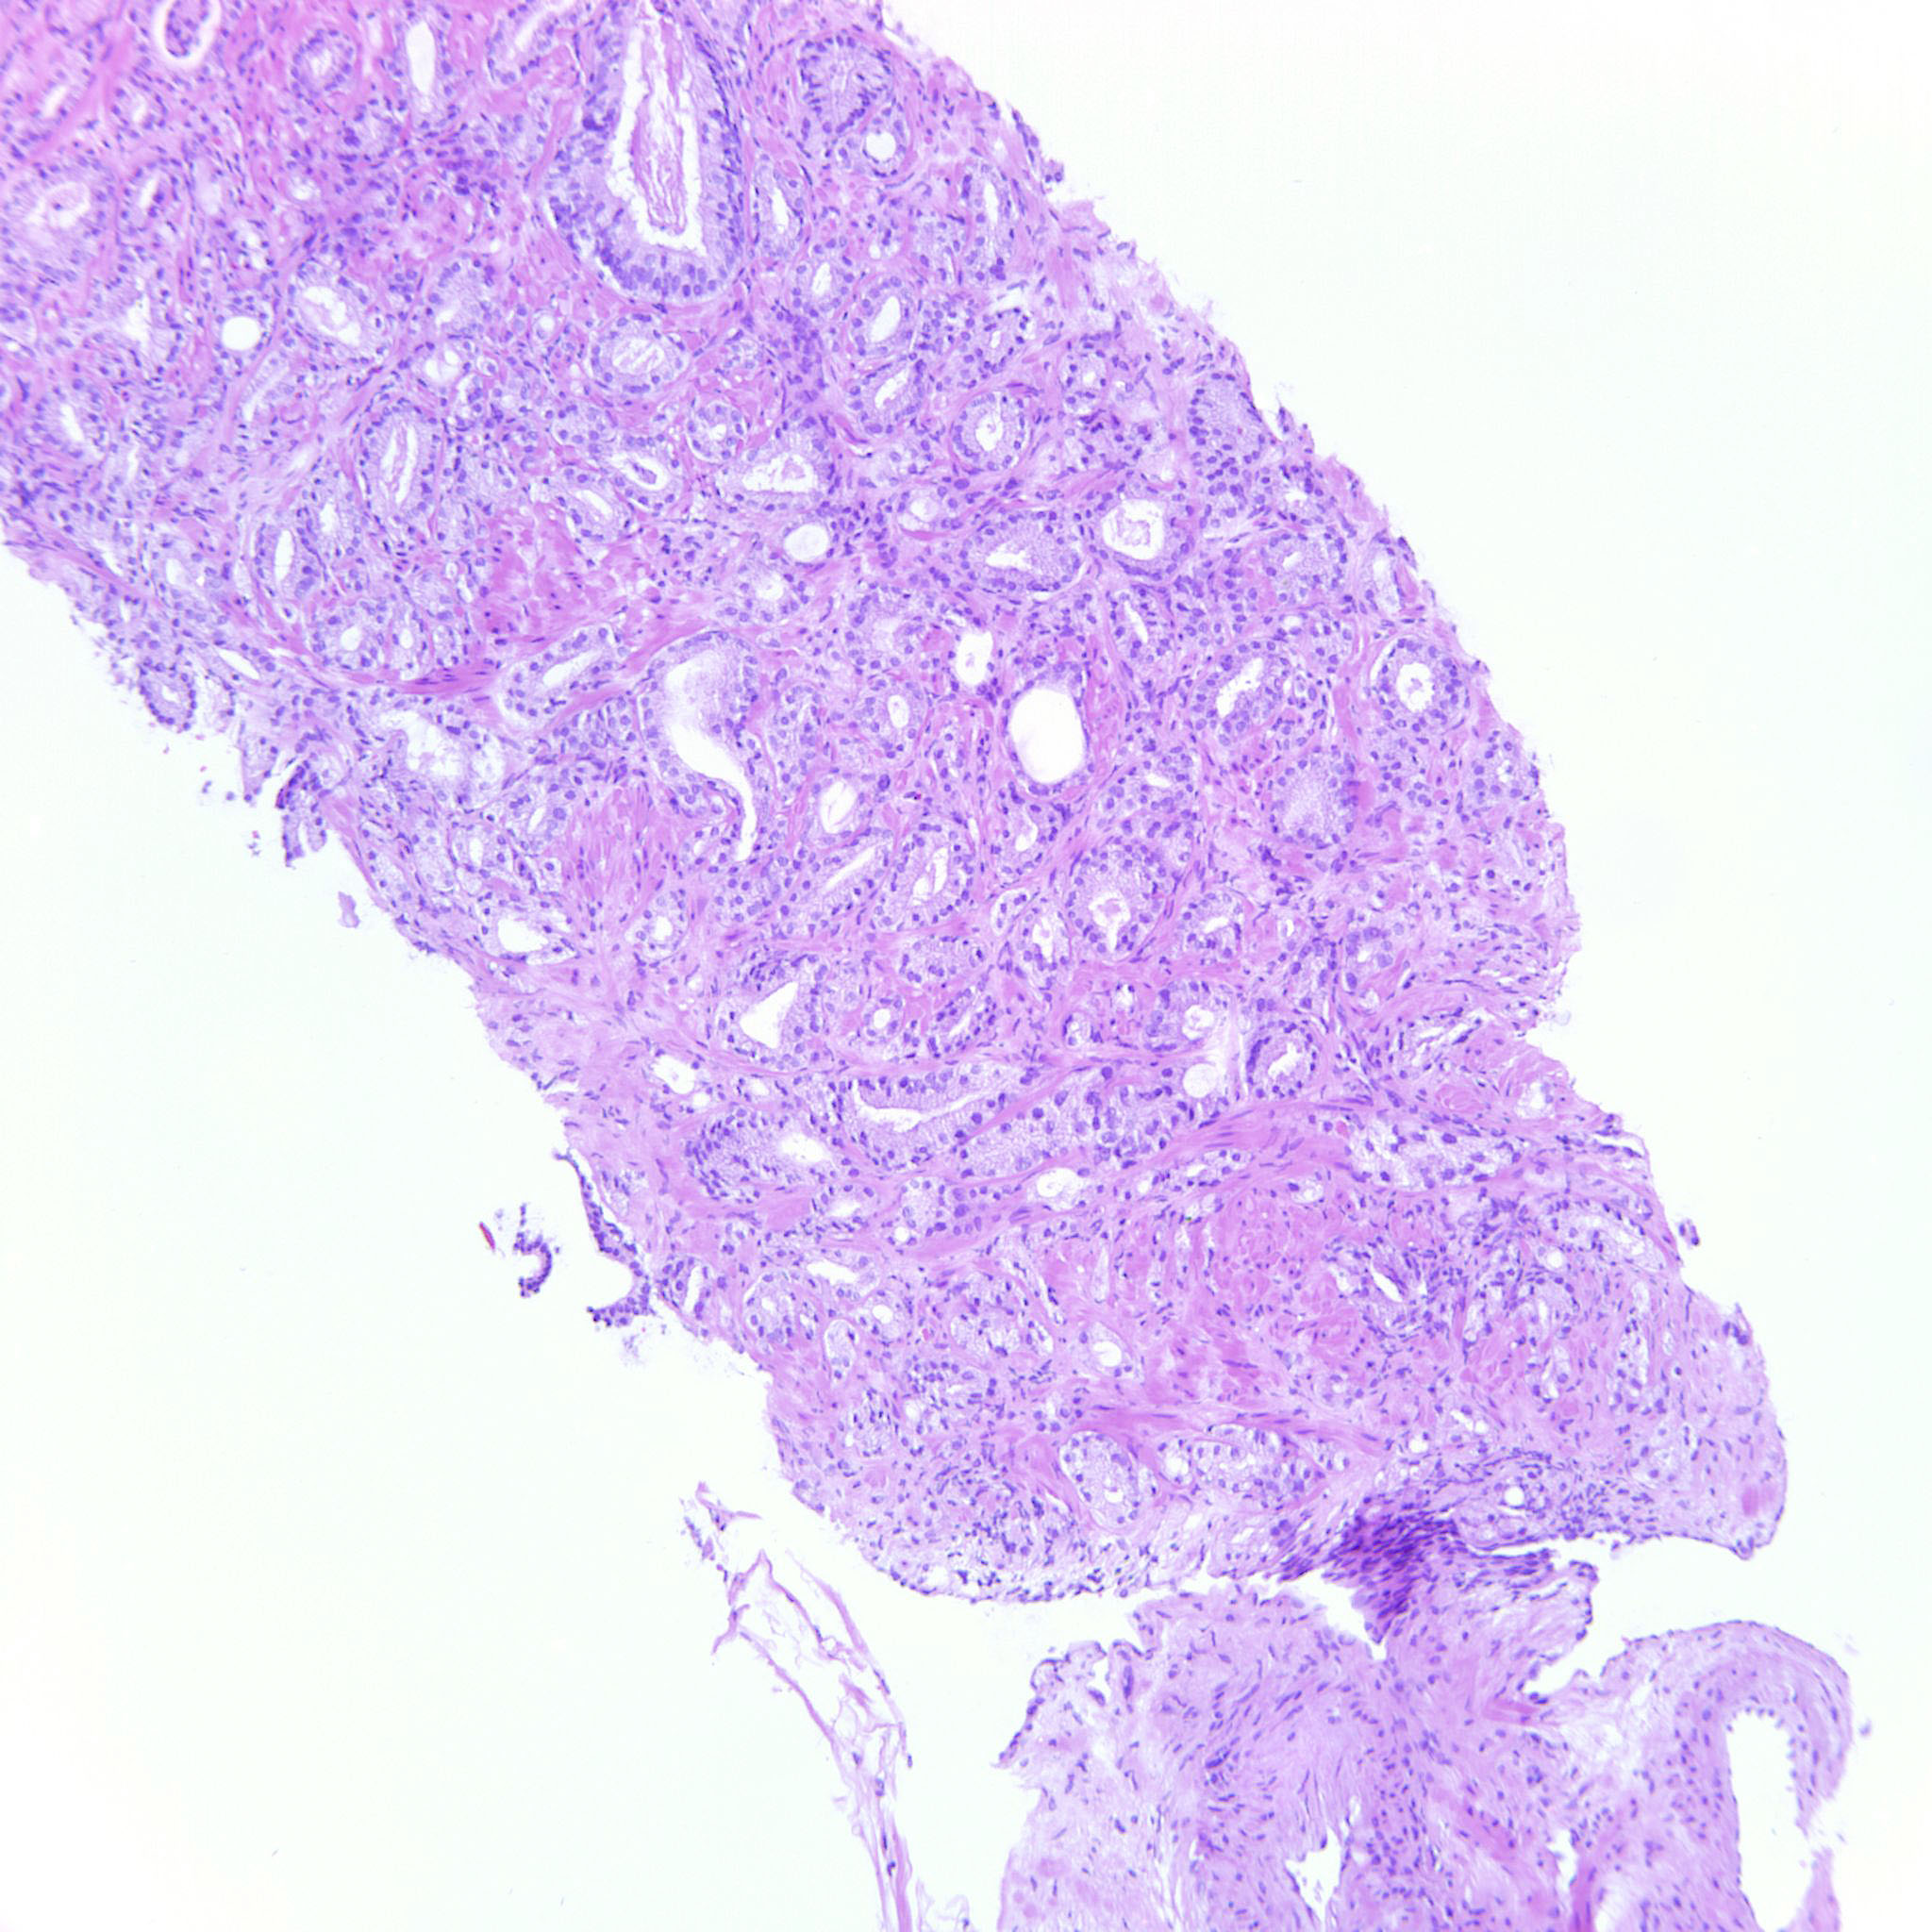

Prostate cancer grading

Case ID: 122